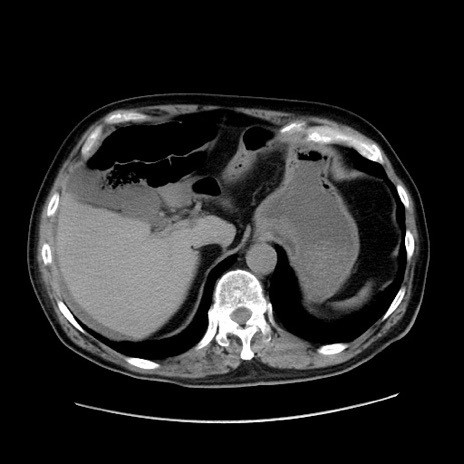

冠状断像

症例30(横断像)

【症例】80歳代男性

【主訴】臍周囲痛

【現病歴】約6時間前から臍下部痛が出現。次第に腹部膨隆・背部痛も生じてきたため来院。背部痛の場所は変化しない。

【身体所見】意識清明、BT 36.3℃、BP  131/87mmHg、P 87bpm、SpO2 100%(RA)、臍周囲自発痛・圧痛あり、反跳痛なし、自発痛部位に一致して板状硬あり、腹部膨隆、腸雑音減弱、CVA tenderness両側陰性。

【データ】WBC 19600、CRP 0.33